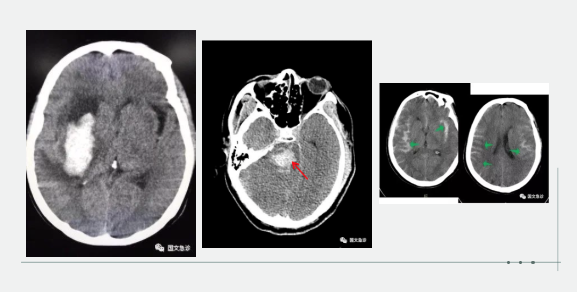

突發(fā)意識(shí)不清兩小時(shí)入院。據(jù)家屬描述“發(fā)現(xiàn)的時(shí)候老爺子躺在地上叫了好幾聲也沒(méi)有反應(yīng),上去推了推也沒(méi)動(dòng)靜趕忙就打120了。根據(jù)該家屬的描述,緊急為患者進(jìn)行查體:該患者意識(shí)成昏迷狀態(tài),查體不合作,雙側(cè)瞳孔等大等圓,呼吸間斷 血壓237/115mmhg。內(nèi)科醫(yī)生進(jìn)一步向家屬了解患者既往血壓情況,該家屬表示:“血壓一直都很高,降壓藥也不按時(shí)吃就難受的時(shí)候吃一片”。進(jìn)一步考慮患者腦內(nèi)出血,立即行頭部CT。為患者打開(kāi)急診綠色通道“遵循檢查或繳費(fèi)的原則”。CT結(jié)果顯示患者左側(cè)大腦半球出血、小腦出血、腦室積血。醫(yī)生立即向家屬交代病情,該家屬哽咽著說(shuō):“你說(shuō)這早上剛還一起吃團(tuán)圓飯呢,一轉(zhuǎn)身的工夫,老爺子就倒地不起了。醫(yī)生您說(shuō)啊,好好的一個(gè)人怎么就腦出血了?以前除了血壓高一點(diǎn)癥狀都沒(méi)有呀!”

突發(fā)意識(shí)不清,1小時(shí)入院。該妻子滿眼淚水地向醫(yī)生訴說(shuō):“我們剛吃完飯,他說(shuō)困了睡一會(huì)兒,這怎么突然就叫不醒了呢?醫(yī)生您快看看,這是咋了呀?”“李先生平時(shí)身體怎么樣?”“我家老李平時(shí)身體可好了,你別看他長(zhǎng)得胖,一年感冒的次數(shù)都少。對(duì)了,就是血壓有點(diǎn)高?!备鶕?jù)家屬描述,立即為患者查體:該患者呈深度昏迷狀態(tài),雙側(cè)瞳孔不等大 左側(cè)3.5mm、右側(cè)5.0mm,血壓250/190,雙側(cè)病理征陽(yáng)性。初步考慮患者腦內(nèi)出血,急行頭部CT檢查。結(jié)果示:右側(cè)小腦及腦干不規(guī)則高密度灶破入腦室,三腦室及四腦室內(nèi)見(jiàn)高密度灶。患者病情危重醫(yī)生立即為患者辦理入院,急忙送往ICU(重癥監(jiān)護(hù)室)進(jìn)行進(jìn)一步治療。